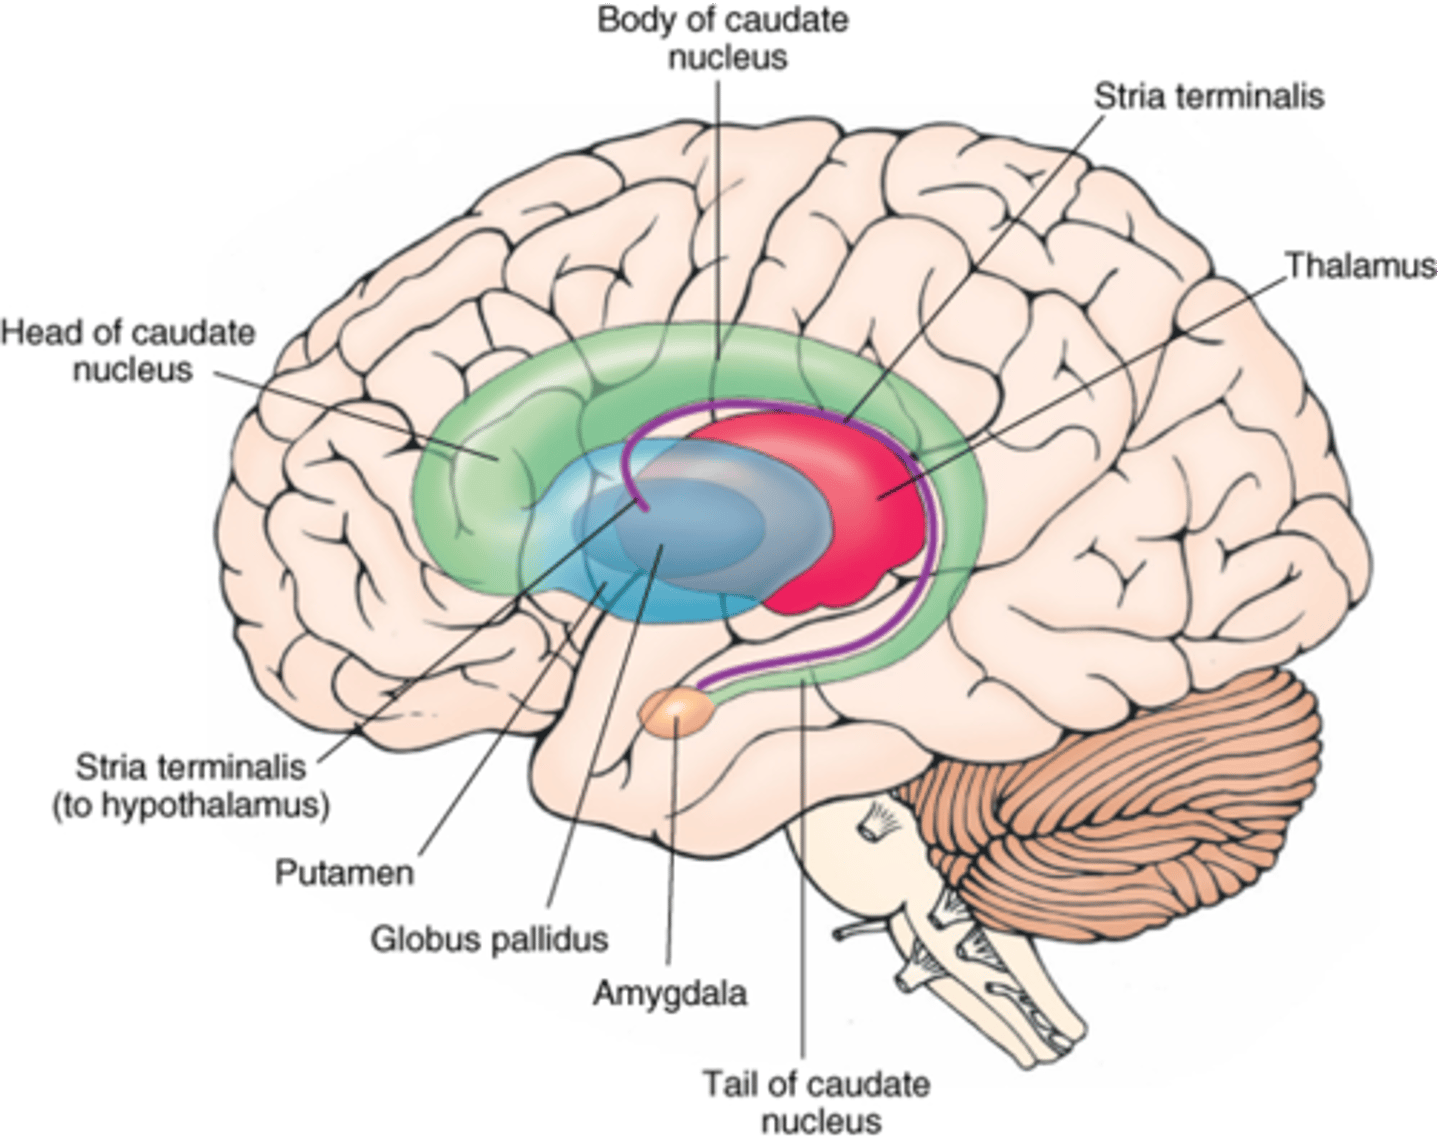

what cerebral gray matter structure is a collection of subcortical nuclei primarily involved in motor control?

basal ganglia

what cerebral gray matter structure has a gate-keeping mechanism for the initiation of motor movement (choosing which actions to allow and which to inhibit)?

basal ganglia

what cerebral gray matter structure has roles in motor learning, executive functions, behaviors, and emotions?

basal ganglia

what are the 3 parts of the basal ganglia? what runs between them?

1. caudate nucleus

2. putamen

3. globus pallidus

internal capsule

what part of the basal ganglia is the C-shaped structure that is most medial?

caudate nucleus

what part of the basal ganglia is medial to the putamen?

globus pallidus

the putamen and globus pallidus of the basal ganglia are collectively called the _______________ nucleus

lentiform